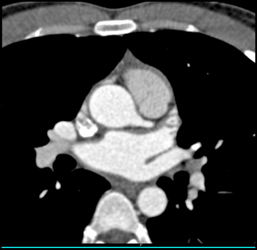

Re-implanted RCA Into Aortic Root